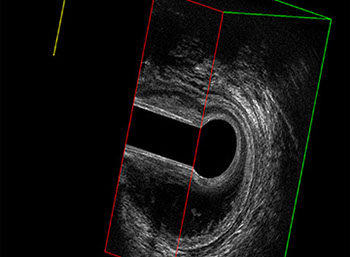

L’ecografia transanale è un esame diagnostico per immagini che consiste nell’introduzione di un trasduttore ad ultrasuoni. Le immagini qualitativamente migliori del canale anale sono ottenute usando un trasduttore rotante, montato in un manipolo rigido, che fornisce un’immagine a 360°. Con le apparecchiature più moderne è anche possibile ottenere immagini tridimensionali.

Proctal dispone di apparecchiatura per ecografia endoanale 3D con sonda rotante.